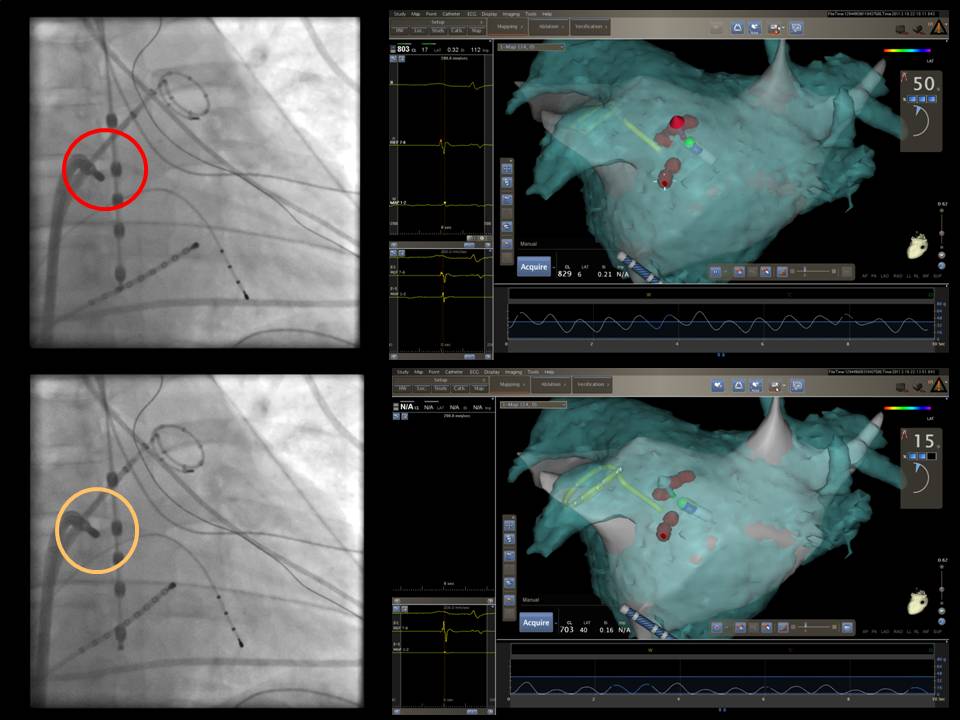

The future path of AF ablation: The Leipzig experience

2015-07-21 18:19